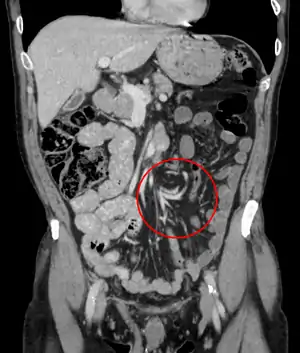

| تصویر نمایانگر مقطعنگاری رایانهای پیچش روده در ناحیه شکمی بوده که از زاویهصفحه کورونال با اشعهٔ X تصویربرداری شده است. DiseasesDB = 13996 | |